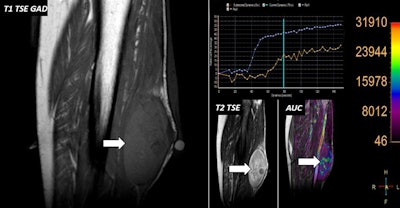

- The use of DCE-MRI enables evaluation of the characteristics of the capillary network with regard to permeability and angiogenesis of MSK soft-tissue lesions using gadolinium-based contrast agents (GBCAs).

- DCE-MRI uses high temporal resolution sequences, usually based on spoiled gradient-echo (SPGR) acquisition techniques with mild to moderate spatial resolution.

- The goal of DCE-MRI is to evaluate the changes of signal intensity within soft-tissue lesions as the GBCA passes through the capillary network, as well as its interchanges with the interstitium.

- Soft-tissue lesion enhancement after GBCA administration on conventional T1-weighted imaging with or without fat suppression is usually linked to increases on the DCE-MRI (perfusion) related parameters.

"First of all, it's important to differentiate between T1-weighted DCE and T1-weighted permeability studies," they wrote. "Both approaches have the same basic sequence design, a dynamic sequence, usually 3D SPGR with high temporal resolution."

The injection rate of GBCAs varies from 3 mL/sec to 5 mL/sec, while for permeability studies, T1 maps prior to GBCA administration have to be acquired.